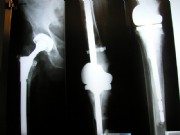

Other examples of knee replacements

Left: Here an existing, elsewhere placed prosthesis was changed because of loosening, and due to bone loss the height had to built up on the shin.

Center left and center right: A modern knee prosthesis with sparing bone removal and sliding surface replacement. Such knee joints are used routinely by us. They are made for the particular patients affected knee.

Right: A so-called "total femur": A solution for desperate cases, in which there is no other way to preserve the limb: The hip (left) and knee (center and right) had to be completely replaced in a session. The anchorage is deep into the lower leg. The hip and knee part are strongly connected through the femur. It is a so-called tumor prosthesis.